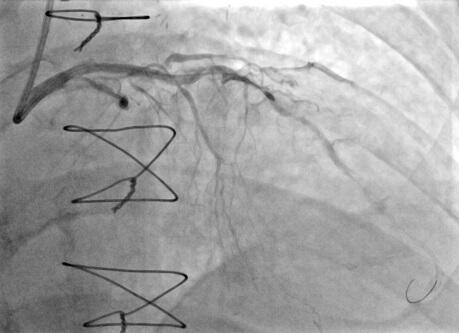

He was referred for PCI, however, despite maximizing support with a guide catheter extension, the mid-LAD could not be crossed even with 1.0-mm balloons. Rotational atherectomy was performed with a 1.5-mm Rotablator burr over a Rota-Floppy guidewire (Boston Scientific) at 160 000 rpm, causing ST-segment elevation due to no reflow. After successful treatment of no reflow with aspiration through a Penumbra catheter and administration of intracoronary nicardipine and adenosine, repeat rotational atherectomy was performed and the LAD lesions were successfully crossed. Upon withdrawal, the burr became entrapped in the mid-LAD within a stented segment (Figure 2, Video 2). Removing the burr by pulling on Dynaglide mode was not successful. We cut the shaft of the burr and advanced a guide catheter extension over the burr into the mid-LAD (Video 3). After multiple attempts and pulling the guidewire, we were able to remove the entrapped burr (Video 4). The burr was covered by stent fragments (Figure 3).